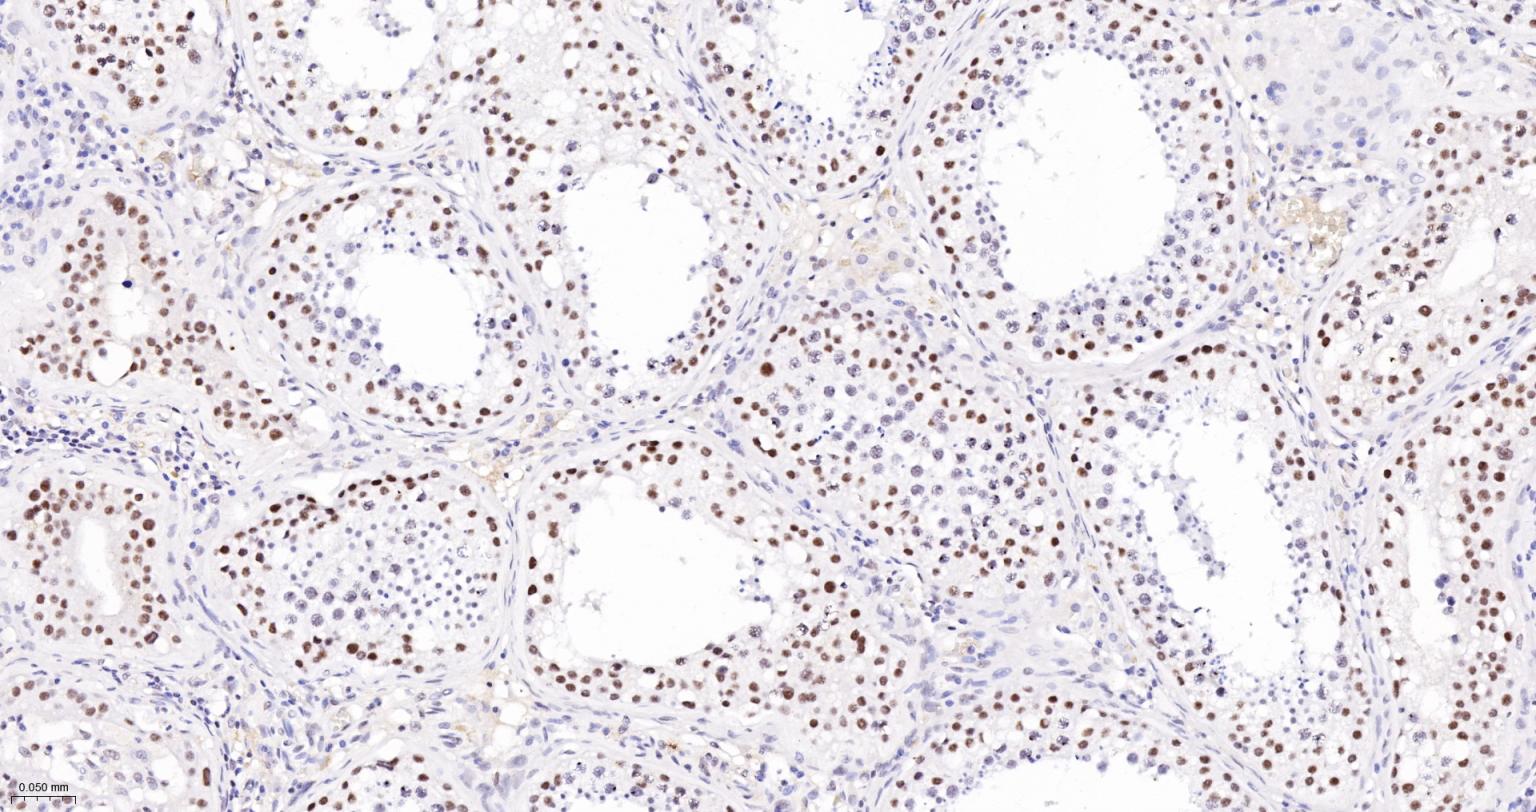

Paraformaldehyde-fixed, paraffin embedded Human Testicles; Antigen retrieval by boiling in sodium citrate buffer (pH6.0) for 15 min; The section was incubated with SIN3A  Monoclonal Antibody, Unconjugated (bsm-61578R) at 1:200 overnight at 4°C, followed by conjugation to the bs-0295G-HRP and DAB (C-0010) staining.

Paraformaldehyde-fixed, paraffin embedded Mouse Testicles; Antigen retrieval by boiling in sodium citrate buffer (pH6.0) for 15 min; The section was incubated with SIN3A  Monoclonal Antibody, Unconjugated (bsm-61578R) at 1:200 overnight at 4°C, followed by conjugation to the bs-0295G-HRP and DAB (C-0010) staining.